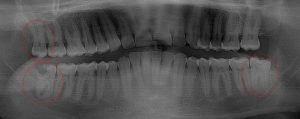

This 19 year old patient has all four 3rd molars present (circled). The roots are +90% formed. Both lower 3rd molars are impacted against the 2nd molars with no chance of further eruption and a +60% probability of decaying before age 30. The patient presented with pain and infection around both lower 3rd molars, requiring immediate extraction